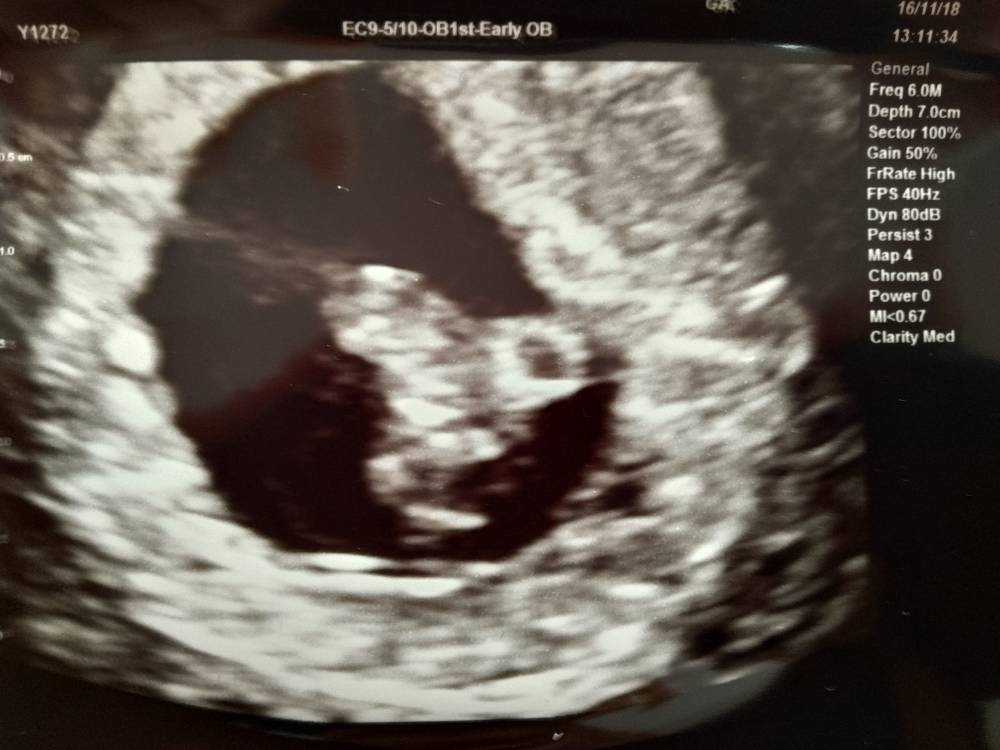

Dziś byłam na pierwszej wizycie, wg OM 8+0 wg USG 7+5, a więc ciąża dwa dni młodsza.

Mały łobuz ma 14,38mm - gigant! A serduszko bije jak dzwoń (150/m) [emoji3526]

Wszystko generalnie super! A kolejna wizyta 21 grudnia [emoji6]

Życzę wszystkim staraczkom tak cudnego widoku! Pozdrawiam!Zobacz załącznik 917108